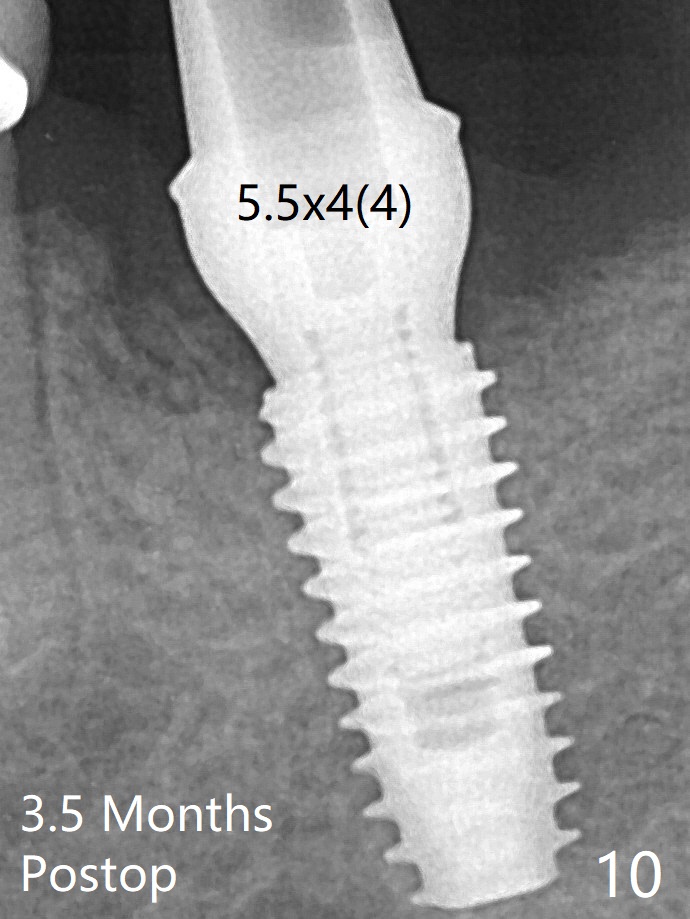

Allograft is placed around the fractured ridge (Fig.6*) before suturing. The ridge appears to have healed nearly 3 months postop (Fig.9). In uncover, the implant plateau is covered with bone; surgical handpiece is used to remove the overlying bone before removing the healing screw. Bone loss in the near future is expected to be minimal if more implants can be placed on the right side. A 5.5x4(4) mm abutment is placed 3.5 months postop (Fig.10).